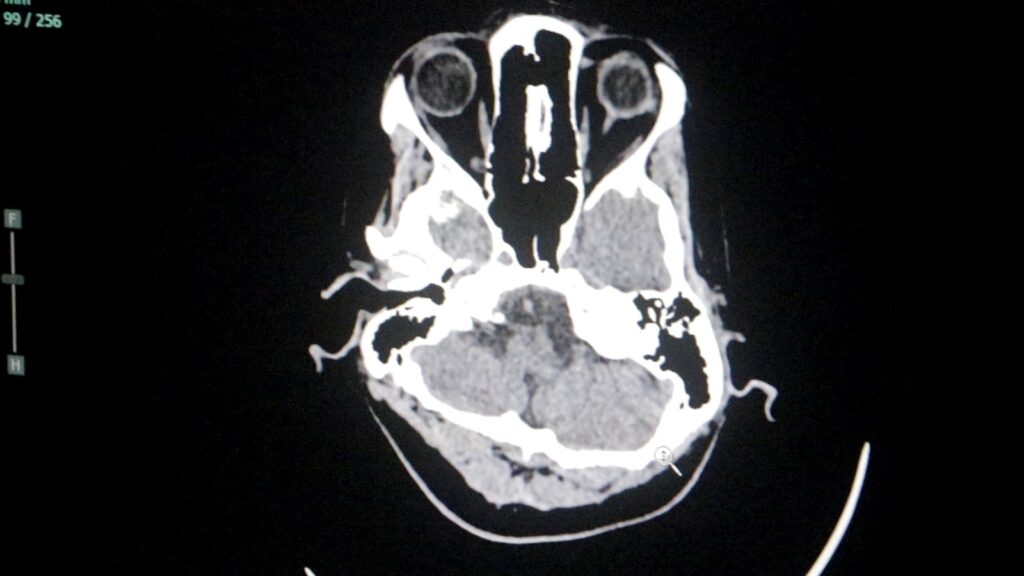

Durante el año, el servicio dio cobertura a cuadros vasculares, tumorales y emergencias neuroquirúrgicas, consolidando al Parque de la Salud como un nodo clave de la alta complejidad neurológica en Misiones.

Durante 2025, el servicio tuvo una intervención destacada en emergencias neuroquirúrgicas, en especial en traumatismos de cráneo asociados a accidentes.

“Se pudo resolver la gran mayoría de los traumatismos de cráneo, siempre con el apoyo fundamental de los servicios de terapia intensiva y anestesia”, remarcó Dei Castelli.